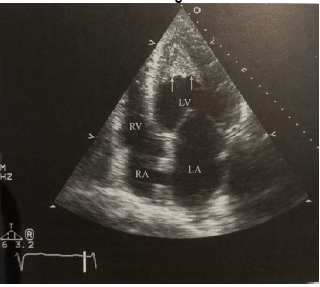

No acometimento das câmaras direitas, pode haver ascite volumosa, hepatomegalia e elevadas pressões de enchimento. E, apresenta um achado característico ao ecocardiograma transtorácico visto na imagem abaixo.

Sobre ele, assinale a alternativa correta.